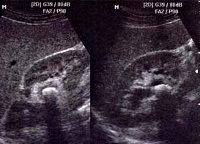

Мочекаменная болезнь у детей подтверждается рентгенологически и с помощью УЗИ-диагностики почек, мочеточников и мочевого пузыря. Важно знать, что уратные камни не обнаруживаются на рентгенограмме. Для подтверждения диагноза используется внутривенная пиелография. Это необходимо и для уточнения локализации конкрементов с целью определения дальнейшей тактики лечения. Возможно проведение томографии для исключения злокачественных новообразований. Поскольку мочекаменная болезнь у детей часто связана с нарушением обмена кальция, осуществляется обследование щитовидной и паращитовидных желез, отвечающих за метаболизм этого микроэлемента в организме.